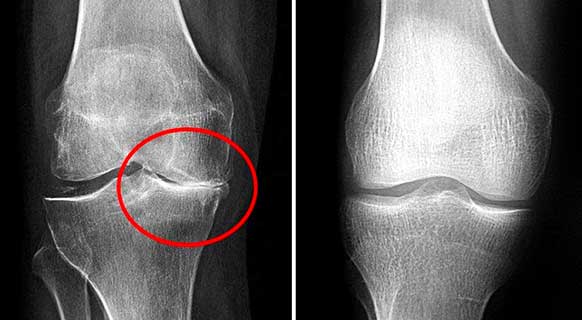

Foto rontgen sendi lutut sebelum dan sesudah mengonsumsi bubuk Invanil

Hasil pengobatan sendi lutut